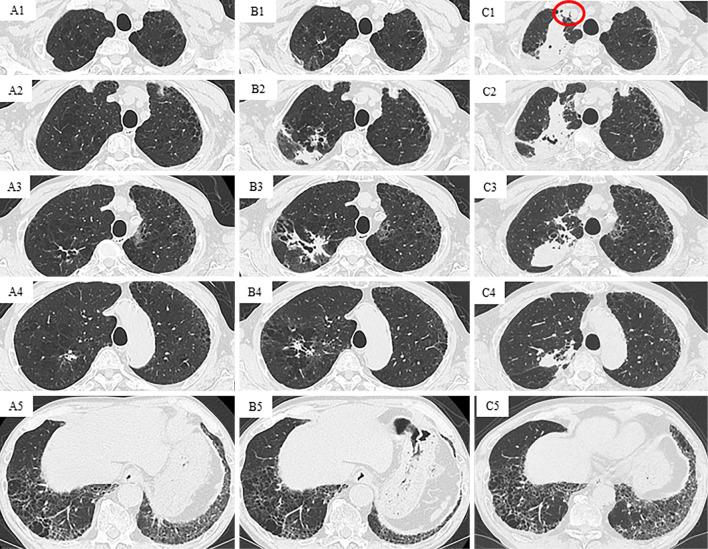

A 69-year-old man with systemic sclerosis and interstitial pneumonia presented with an abnormal shadow in the right upper lung lobe. A thoracoscopic needle biopsy was performed on the right upper lobe lesion, and Mycobacterium malmoense was identified by 16S rRNA and rpoB gene sequencing. Surgical treatment was performed to obtain a radical cure, and lung squamous cell carcinoma and M. malmoense infection were detected in the resected specimen. We herein report the first case of the successful treatment of a patient with pulmonary M. malmoense infection and concomitant lung squamous cell carcinoma.

一名患有系统性硬化症和间质性肺炎的69岁男性,右上肺叶出现异常阴影。对右上叶病变进行了胸腔镜针吸活检,通过16S rRNA和rpoB基因测序鉴定出马尔默分枝杆菌。为实现根治进行了手术治疗,在切除标本中检测到肺鳞状细胞癌和马尔默分枝杆菌感染。我们在此报告首例成功治疗肺部马尔默分枝杆菌感染合并肺鳞状细胞癌患者的病例。